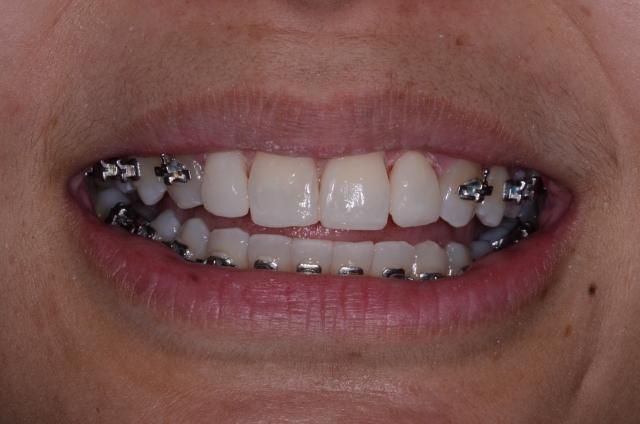

The good news is that if our patients really want the best solution and we do a good job of communicating with them, most of the time they[ll do the orthodontics. Once they’re committed, the first step is to have the orthodontist move the teeth into the proper position and then, if needed, take off the brackets (Fig. 7) so you can resize the teeth (Fig. 8).

One important thing to note is that these teeth have been resized but they’re still not aligned correctly because the bonding to resize them was done according to the root angulation and desired final size, not the current position. We don’t expect it to look perfect here — all we want is the right size and shape. We don’t care about alignment, and in fact, if the roots are still tipped, our bonding must follow that.